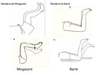

MANOBRA DE MINGAZZINI

MANOBRA DE BARRE

COMO FUNCIONA A MANOBRA DE MINGAZZINI E BARRE?

MINGAZZINI: Avaliar assimetria, duração (1 – 2 min é o normal)

BARRE: Analoga ao mingazzini, mas paciente deitado